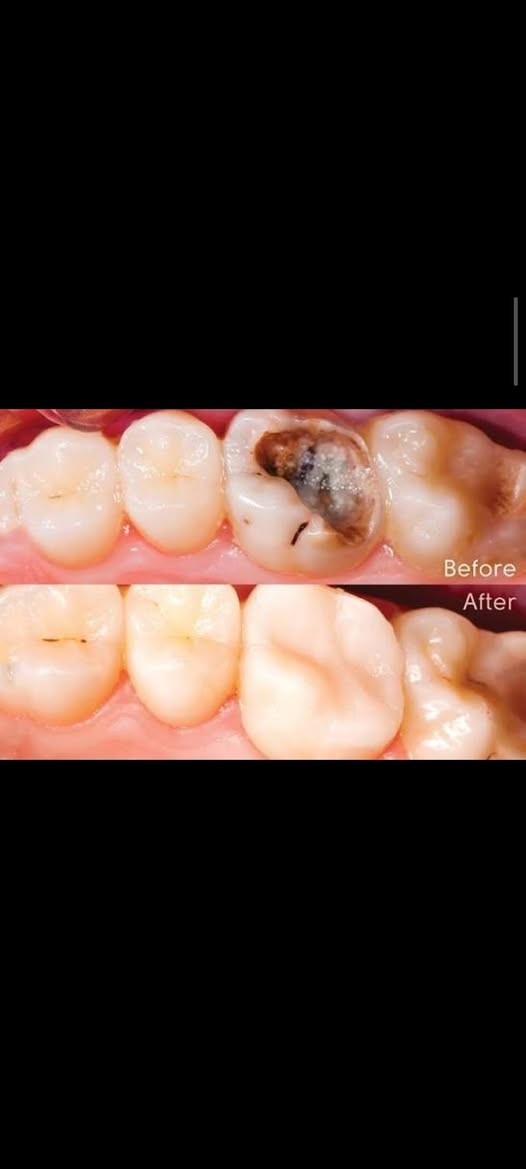

علاج مجاني السلام عليكم ورحمة الله وبركاته للمرضى الاعزاء يتوفر لدينا :- قلع سن. حشوة اعتيادية. تنظيف الاسنان من التكلسات. تبديل حشوة قديمة بحشوة ضوئية. طقم اسنان للفكين الاسفل و الاعلى. مجاني في عيادات جامعة النور التخصصية لطب الاسنان بإشراف الدكاترة المتخصصين في طب الاسنان الاستفسارات والأسئلة العامة الاتصال على الرقم التالي : *********** الدكتور واثق عبدالله حسن ابتسم وانت مرتاح